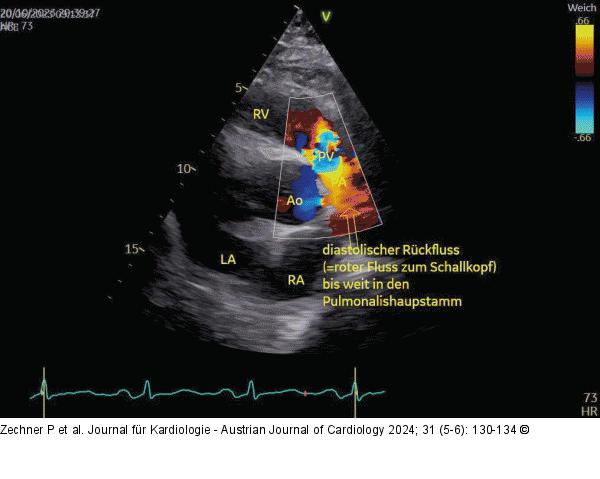

Abbildung 4: Echo Parasternale kurze Achse über Aorta und PK; Z. n. OP bei TOF, schwere PI. Im Farbdoppler sieht man nur in der frühen Diastole den roten Rückfluss (rot = zum Schallkopf) bis weit in den Pulmonalishauptstamm bzw. sogar bis in die PA-Äste. ACHTUNG: Da der Rückfluss nur in der frühen Systole stark ausgeprägt ist, kann er leicht unterschätzt werden. |

Parasternale kurze Achse über Aorta und PK; Z. n. OP bei TOF, schwere PI. Im Farbdoppler sieht man nur in der frühen Diastole den roten Rückfluss (rot = zum Schallkopf) bis weit in den Pulmonalishauptstamm bzw. sogar bis in die PA-Äste. ACHTUNG: Da der Rückfluss nur in der frühen Systole stark ausgeprägt ist, kann er leicht unterschätzt werden. |